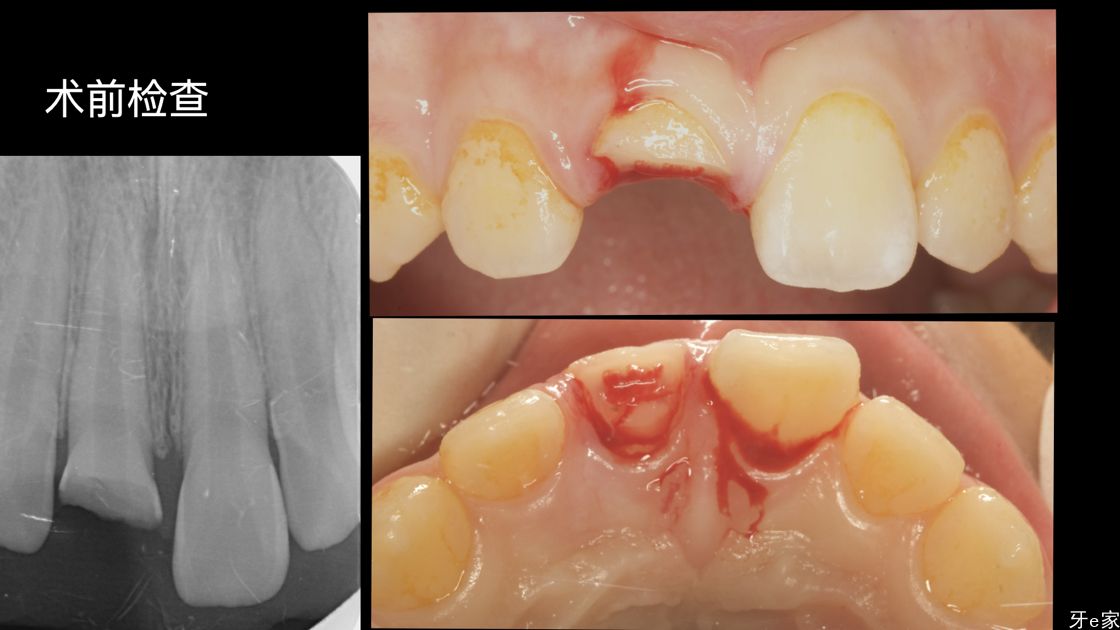

术前检查